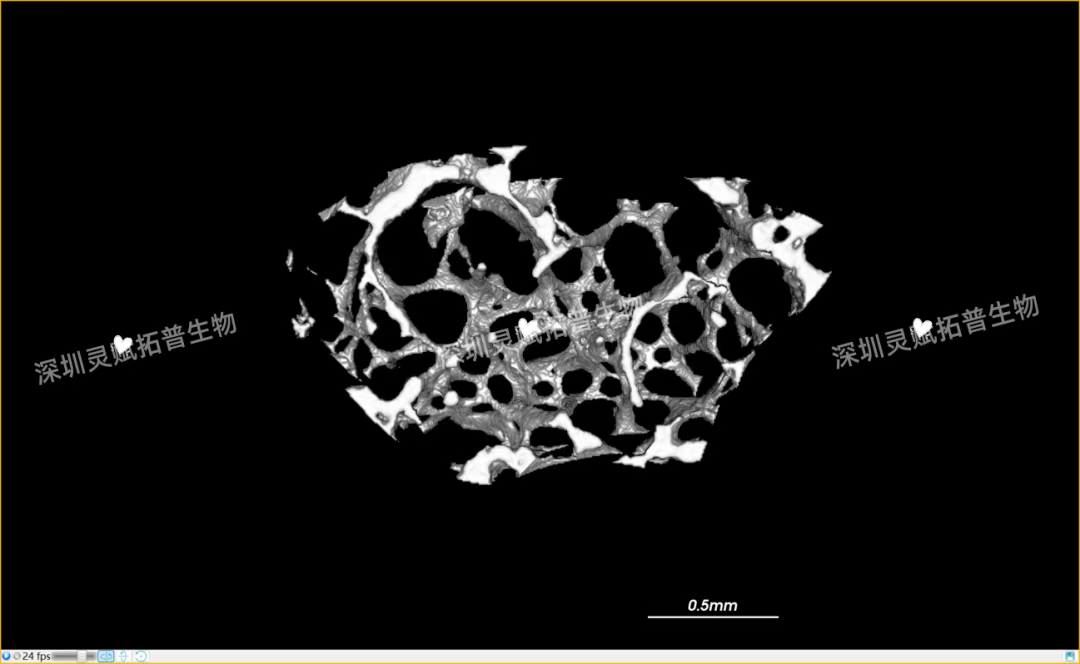

以小鼠股骨检测为代表,带大家直观感受J9国际站 J9 生物的服务实力:

本次实验对 E2 系列(E2-1、E2-2、E2-3)共3个小鼠股骨样本进行标准化扫描,取得了 0.5mm、2mm 等不同尺度的清晰成像,不仅直观呈现了股骨的宏观形态,更精准捕捉到骨小梁排列、皮质骨厚度等微观细节,为后续骨质疏松、骨修复等相关研究给予了可靠的量化数据支撑。

下附E2系列的典型案例:小鼠股骨扫描成像图